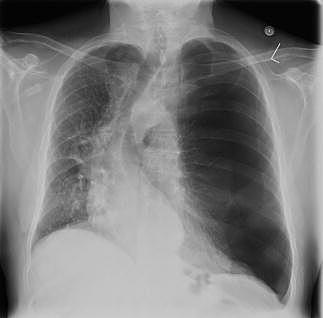

En 64-årig mand vågnede med åndenød og en skarp smerte tværs over brystet natten efter en glad aften i Cirkusrevyen. Patienten var læbecyanotisk, dyspnøisk og havde forlænget expirium. Ved ankomsten til sygehuset var saturationen 90% uden ilt, og blodtrykket var 190/90 mmHg. Et elektrokardiogram viste sinustakykardi med frekvens 103. Der blev fundet høje »pulmonale« p-takker, men normal hjerteakse. Der var ingen tegn på iskæmi eller belastning. Ved stetoskopi var der fravær af respirationslyd på venstre thoraxhalvdel og nedsat thoraxbevægelighed. Ved en røntgenundersøgelse af thorax afslørede man en stor pneumothorax på venstre side, hvilket medførte svær deviation af cor og øvrige midtlinjestrukturer. Patienten blev behandlet med akut pleuradrænanlæggelse.

Patienten var tidligere kardiopulmonært rask fraset en mangeårig, mild, kronisk obstruktiv lungesygdom, som aldrig havde været indlæggelseskrævende. Han havde ikke været udsat for traumer. Det må antages, at patientens trykpneumothorax var udløst af et af aftenens mange voldsomme latteranfald.